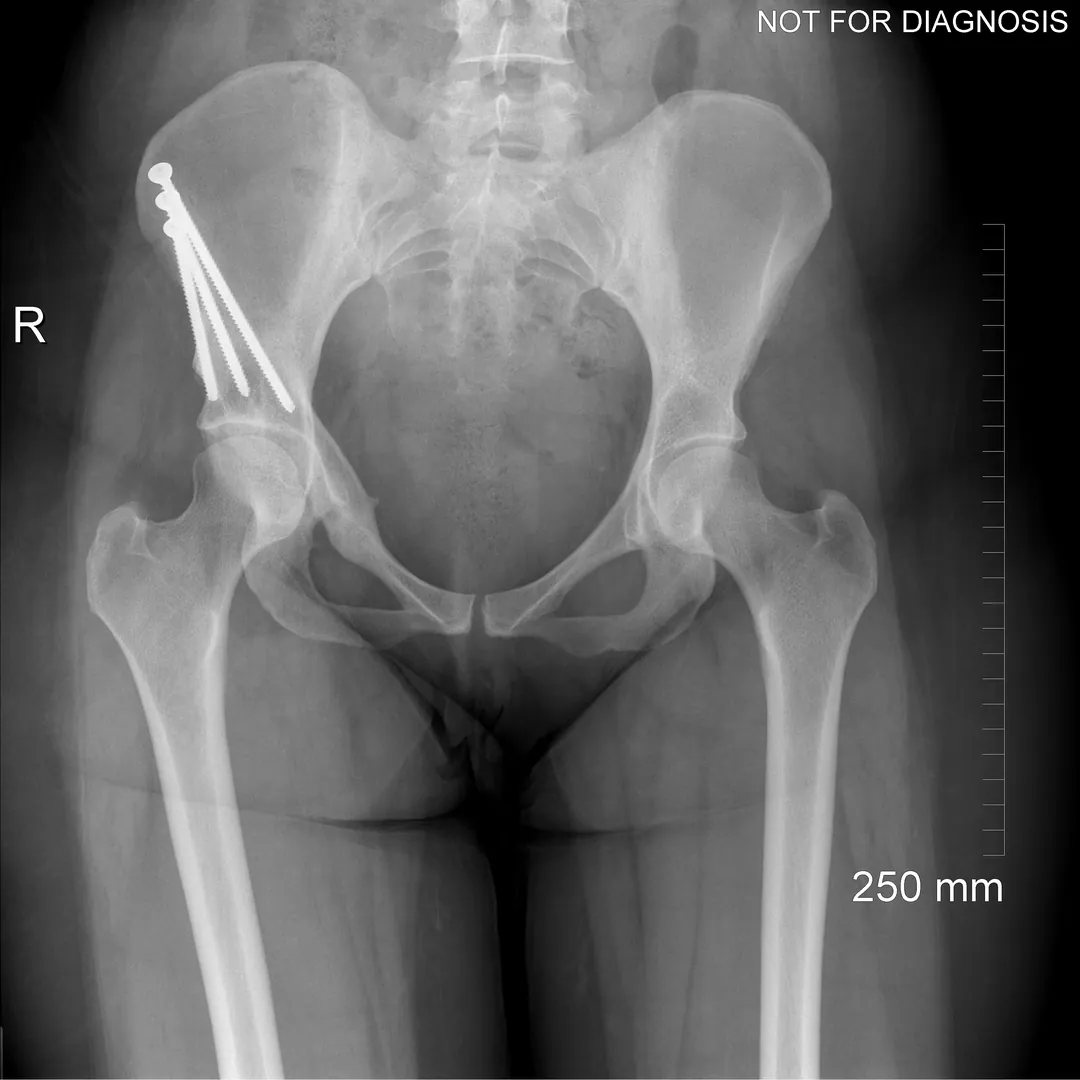

During a PAO, the surgeon carefully cuts the bone around the hip socket and repositions it to provide better coverage of the femoral head. The socket is then fixed in its new position using screws. The goal is to improve hip stability, reduce pain, and preserve the patient’s natural hip joint.

• Diagram 3: Hip After Periacetabular Osteotomy (PAO)

Diagram 3: Hip After Periacetabular Osteotomy (PAO)

• Acetabulum repositioned to improve femoral head coverage

• Load more evenly distributed across the joint

• Screws shown securing the acetabulum in its new position

These diagrams are commonly used in clinic to help patients visualize the problem and understand how PAO corrects hip mechanics. Dr Grammatopoulos will review your X-rays alongside these illustrations to explain your individual anatomy and surgical plan.

Screw Removal

In most cases, the screws are left in place. However, if they cause irritation, removal can be considered after the bone has healed, which is typically 9-12 months after the initial PAO.